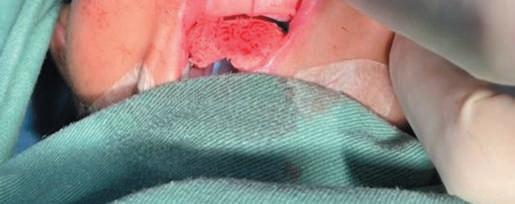

6. Fazer uma incisão sublabial de 1,5 cm com lâmina 15 até o osso, tomando cuidado para não danificar o osso fino que recobre os germes dentários (Fig. 1-2).

7. Realizar dissecção subperiosteal para expor a espinha nasal anterior e o assoalho de cada narina, permanecendo anterior aos cornetos inferiores para evitar lesão ao sistema nasolacrimal (Fig. 1-3).